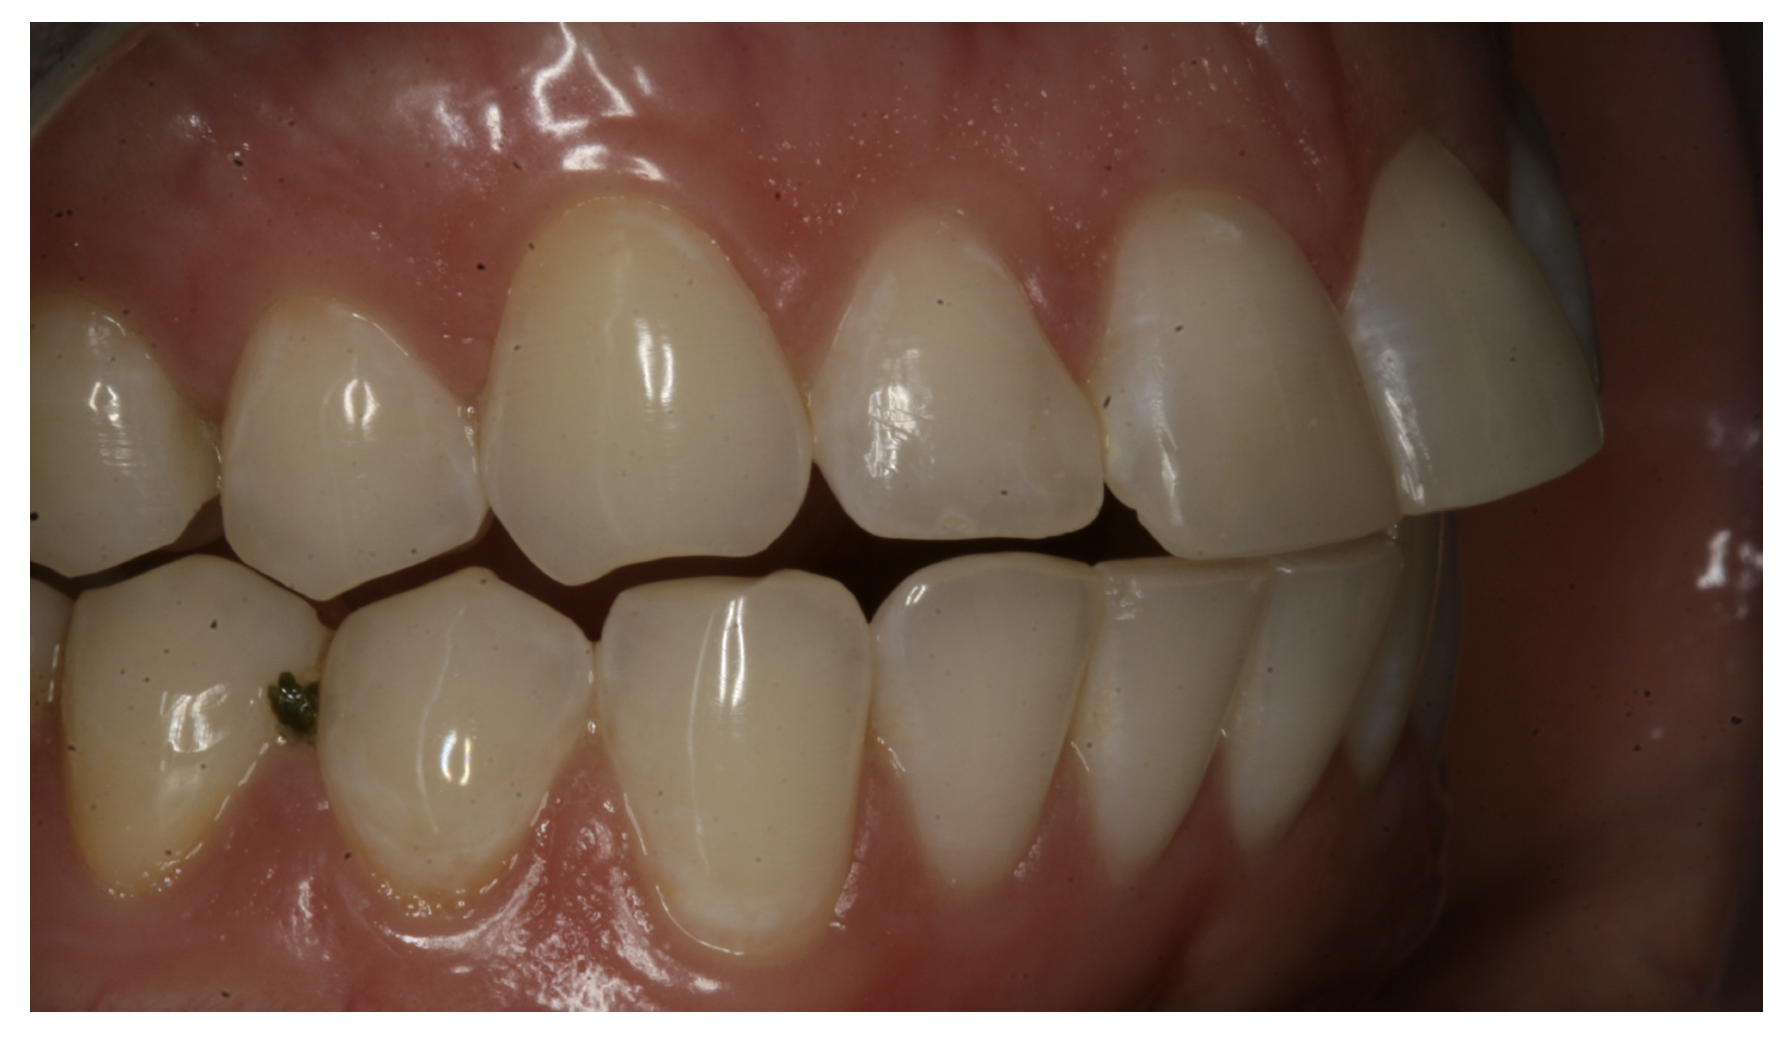

For the case in Figure 9 through Figure 11, the patent presented for an initial consultation with bonding completed on teeth Nos. 7 through 10 a few years prior with a chief complaint of not liking the way the resin bonding looked and how it was wearing. Up to this point, the bonding had repeatedly chipped and been repaired three times already. The patient's canines also exhibited signs of incised wear and flattening, which she did not like. Based on the patient's goals for her smile and her financial budget, she elected to have porcelain veneers completed on teeth Nos. 6 through 11. The total esthetics of the case design were somewhat limited given that the patient's esthetic zone included her posterior teeth and mandibular anterior teeth. Therefore, the color and characteristics of the veneers had to match her existing dentition closely.